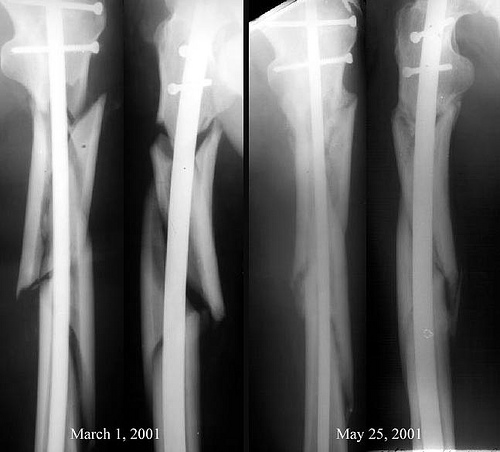

Using old bicycle parts (so the legend goes) Ilizarov constructed a multi-ring circular frame. He deliberately fractured a patient’s bone and inserted the apparatus; as the patient’s bone began to heal and grow back together, Ilizarov would adjust and tighten the frame, stretching the healing bone out millimeter by millimeter. (Yes, this process is uncomfortable . . . and now the playground punks will probably call you “freaky Robo Joe” because you have giant metal rings and spikes protruding from your leg. Sometimes you just can’t win. ) Over time, a limb with an Ilizarov device can be lengthened significantly; when the procedure is finished, the apparatus is removed and voilá, the patient has a longer leg. (And, finally the chance to kick some major butt.) An Ilizarov device can also be used in certain types of messy and complicated fractures where other techniques (like the above mentioned intramedullary rod) are not feasible. To this day, the Ilizarov device is one of the most common methods employed in limb-lengthening procedures—although these days the apparatus is made of materials somewhat more sophisticated than Gavril’s old bicycle.